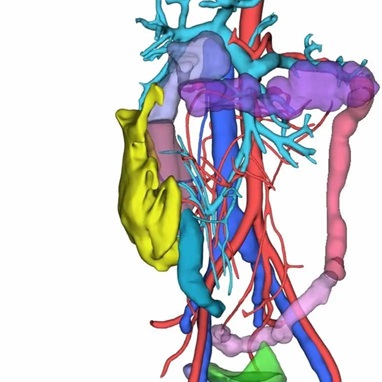

腹腔消化道的血液供应主要来自腹主动脉的分支,包括肠系膜上动脉和肠系膜下动脉。其静脉回流则较为特殊:血液由肠系膜上静脉和肠系膜下静脉等收集,汇合后形成门静脉。门静脉将血液输入肝脏进行代谢后,再经肝静脉汇入下腔静脉,最终返回心脏。

腹腔肿瘤包括肝肿瘤、脾肿瘤、肠系膜肿瘤等。三维重建技术在腹腔肿瘤的诊断、治疗和预后评估中具有重要作用。通过三维重建,可以更全面地展示肿瘤的位置、形态、侵犯范围以及与周围器官的关系,有助于医生制定更精确的手术方案和预后判断。此外,三维重建还可以用于评估手术效果和指导进一步的治疗,例如在机器人辅助手术中,三维重建技术可以提供更精确的手术导航和操作指导。

在胃癌手术前行双源CT增强扫描和腹腔血管三维重建,明确胃周血管的位置、解剖学特点及其变异情况,做好详细的手术预案,可明显缩短手术时间。、